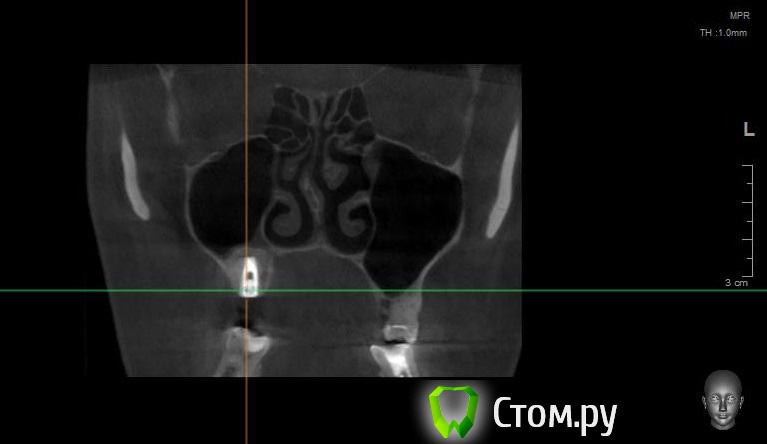

Bier Опубликовано 14 апреля, 2014 Поделиться Опубликовано 14 апреля, 2014 Покажите пазухи на кт свежем еще раз, в предыдущем сообщении вы другую пазуху показали, с зубами Ссылка на комментарий

Майло Опубликовано 14 апреля, 2014 Автор Поделиться Опубликовано 14 апреля, 2014 (изменено) Выкладывала другую область, так как думала, может из-за нее воспаление. Не знаю, какой смысл в этих снимках, если симптомы сохраняются, а снимки вроде чистые? Еще лор, который хирург, сказал, хорошо бы ревизию сделать, если было такое сильное кровотечение после имплантации мог образоваться тромб, а когда пошла зелень мог инфицировать, правдо что точно я не поняла и не стала уточнять. Сказал, что он таким не занимается и чтобы я шла где делала, а там врач сказал, что вообще еще ни разу никому ничего не вынимал и "ревизии" не делал. Вот так вот... Изменено 14 апреля, 2014 пользователем Майло Ссылка на комментарий

Bier Опубликовано 14 апреля, 2014 Поделиться Опубликовано 14 апреля, 2014 Странно, у вас абсолютно чистая пазуха. Если у Вас есть фейсбук, могу вас сконтачить с более толковым ЛОРом Просто "зеленые сопли" о которых вы говорите должны где-то быть. Ссылка на комментарий